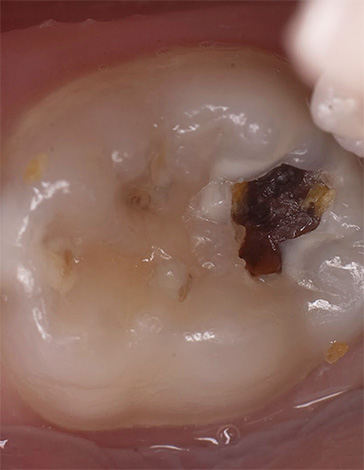

La fotografia sotto mostra un esempio di una cavità già formata durante il trattamento della carie profonda: